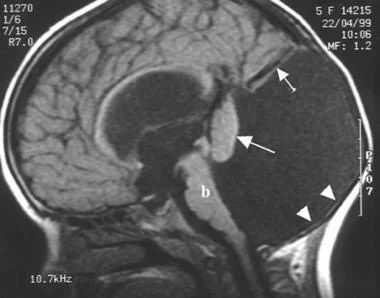

ЭхоКГ:14.07.06 - небольшое увеличение правых отделов сердца, вторичный ДМПП 4мм, клапанный аппарат не изменен. ООО - 2,5мм -заключение: ВПС, небольшой вторичный ДМПП, небольшая перегрузка правых отделов, контроль через 3 мес. Осмотрен генетиком - МВПР, не исключается СДУ, взят ан крови на кариотип 24.07 - 46,ХУ. ЯМРТ головного мозга от 28.07.06 - срединные структуры не смещены, гипоплазия червя и полушарий мозжечка с расширением большой затылочной цистерны и цистерны четверохолмия до 25-40 мм в поперечнике, расширены субарахноидальные пространства в лобных и височных областях, желудочки обычной формы, тела боковых желудочков до 13 мм, задние рога - до 16 мм, третий желудочек 3 мм, четвертый 7 * 10 мм.

Заключение: вариант СДУ. Умеренно выраженная смешанная гидроцефалия. Нейрохирург - показаний для оперативного лечения нет. Осмотр окулиста от 25.07.06 - опалесценция роговицы, сосуды на глазном дне сужены, наблюдения в плане врожденной глаукомы, от 1.08.06 - опалесценция роговицы уменьшилась.

Дополнительно отмечаются истончение мозолистого тела, атрофические изменения перивентрикулярного белого вещества.

Заключение: МР-картина варианта мальформации Денди—Уокера. Внутренняя тетравентрикулярная гидроцефалия. Послеоперационные изменения в теменно-затылочных областях (см. рисунок).